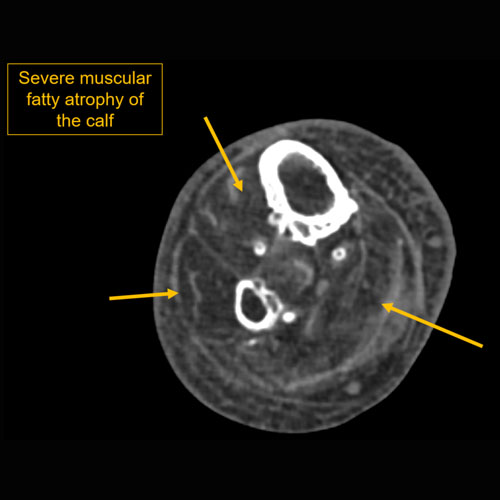

Section 1 Submit Findings CB1118 Findings Limitations There is patient motion or other limitations. Yes No Skin/Hypodermis There is edema or hyperenhancement. Yes No There is soft tissue ulceration or sinus tract. Yes No There is gas or foreign body. Yes No There is confluent hypoenhancement to suggest phlegmon, suppuration, abscess, or drainable fluid collection. Yes No Investing/Intermuscular Fascia There is edema, thickening, or hyperenhancement. Yes No There is hypoenhancement or gas along the fascia. Yes No There is bulging of the fascia. Yes No Muscles There is edema or hyperenhancement. Yes No There is hypoenhancement, lack of enhancement, or organized fluid collection. Yes No There is fatty atrophy. Yes No Bones There are fractures. Yes No There is periosteal reaction, osseous destruction, or focal demineralization to suggest osteomyelitis. Yes No There is cloaca, sequestrum, or involucrum. Yes No There is a subperiosteal or intra-osseous abscess. Yes No Visualized Joints There is a joint effusion. Yes No There is malalignment, degenerative changes, or other gross internal derangement. Yes No Miscellaneous There is tenosynovitis. Yes No Major visualized vascular structures are abnormal. Yes No Major visualized nerves are abnormal. Yes No